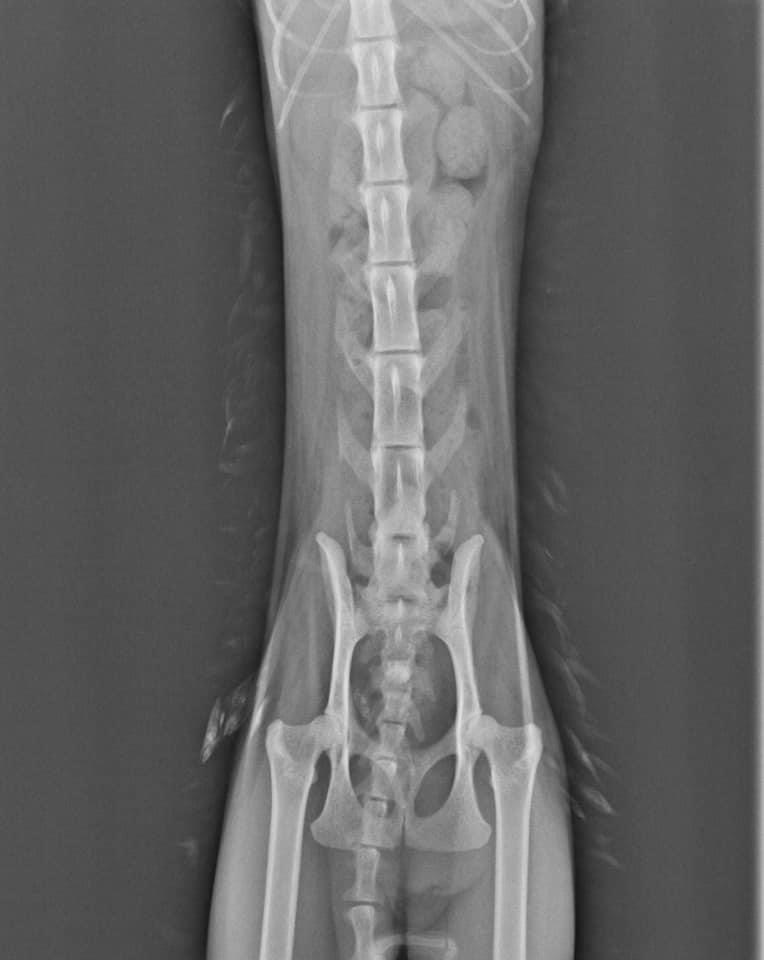

慎重起見。先幫阿咪做個X光檢查。果不其然。找到問題點了。

阿咪膀胱有結石。而導致血尿。但因為阿咪實在太瘦了。體重也只有2.4公斤。

醫生怕立即手術阿咪會對麻醉上有風險。